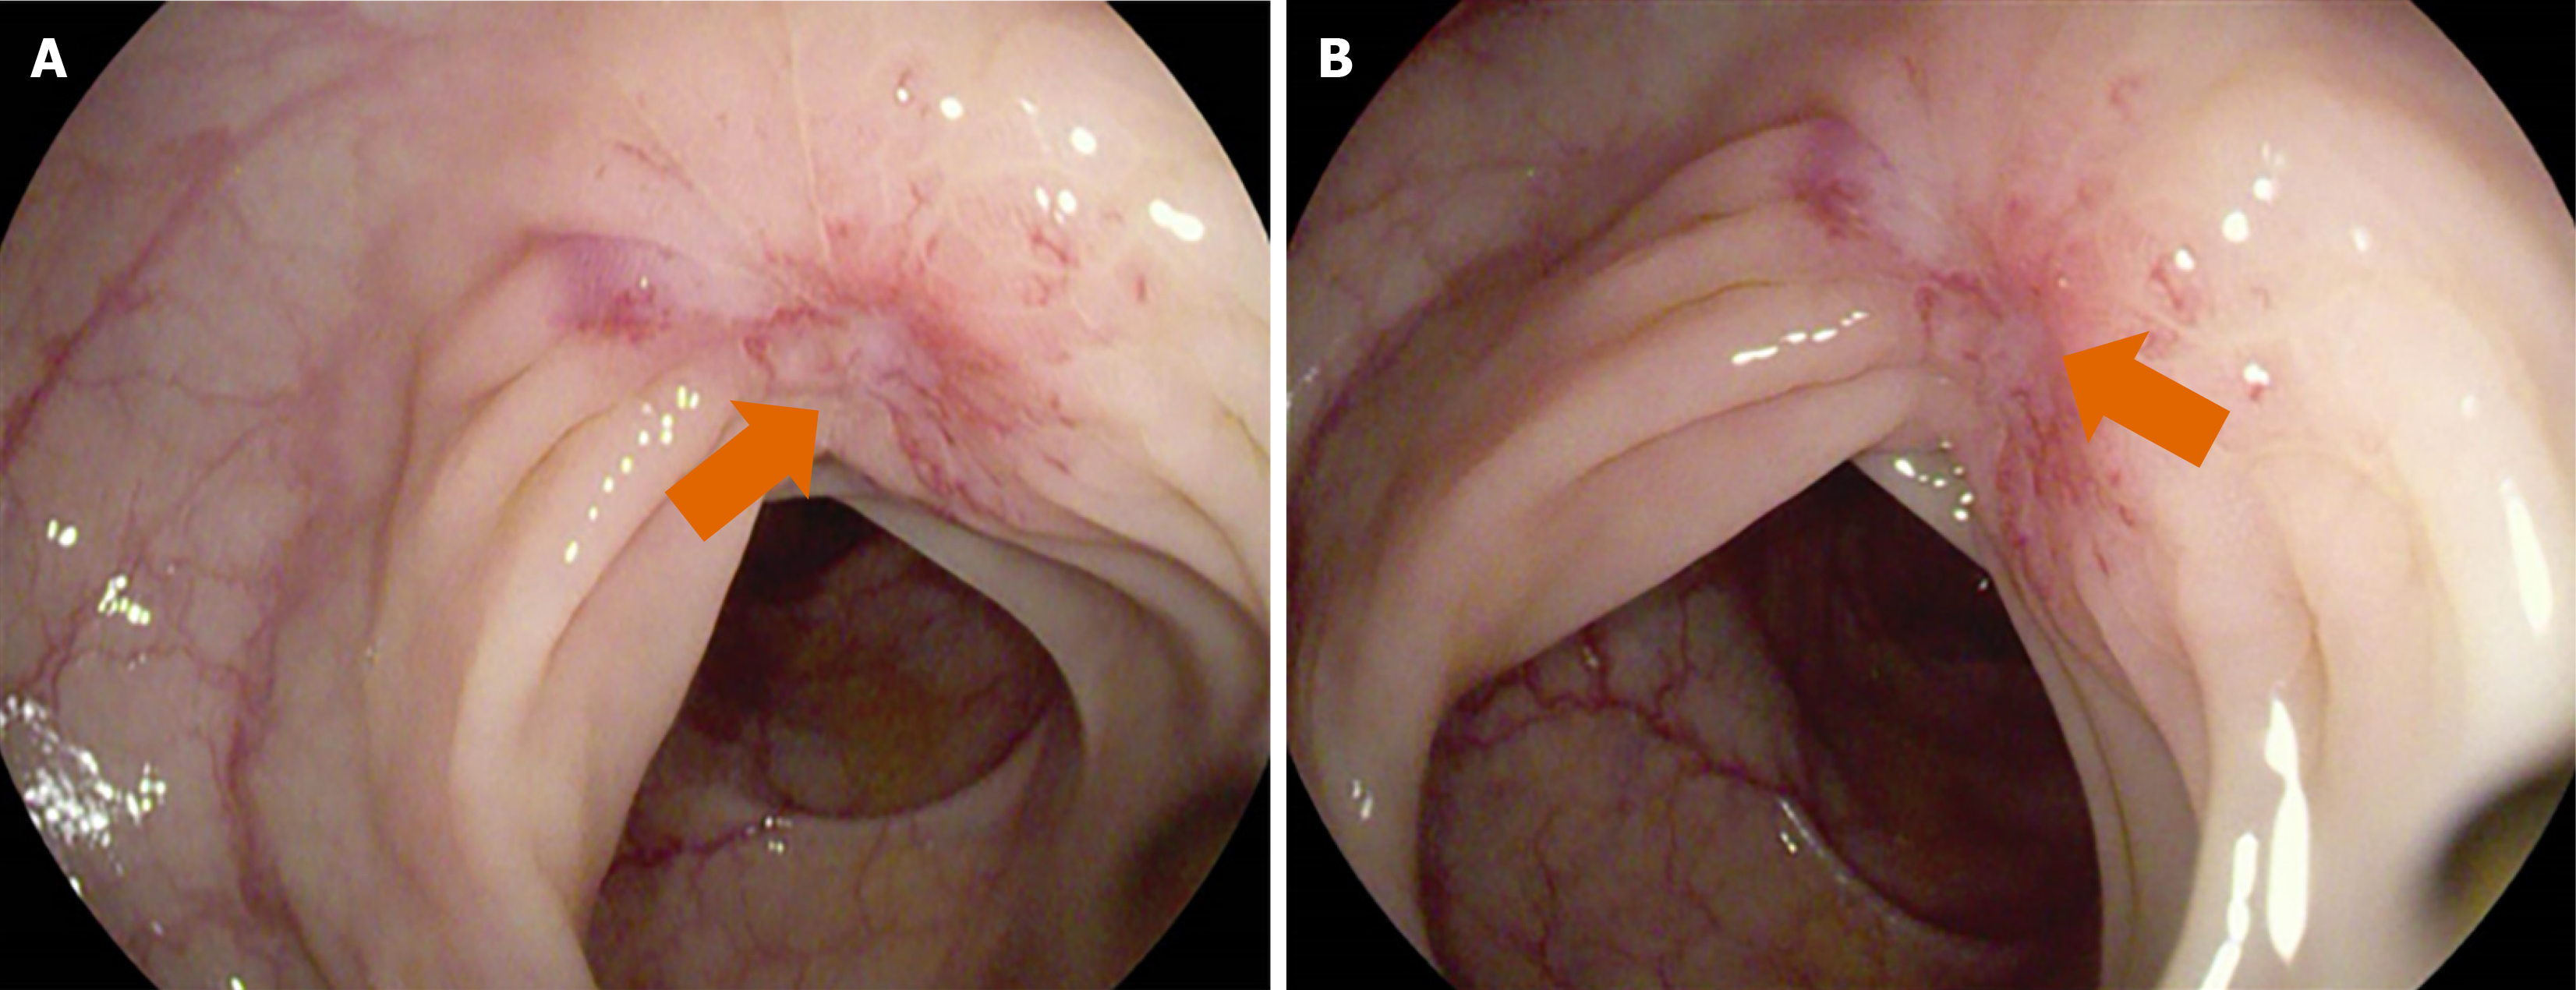

Figure 2 Colonoscopy.

A and B: An infiltrative lesion was observed in the sigmoid colon approximately 35 cm from the anus, with surrounding mucosa converging toward the center and exhibiting fragile texture (orange arrow).